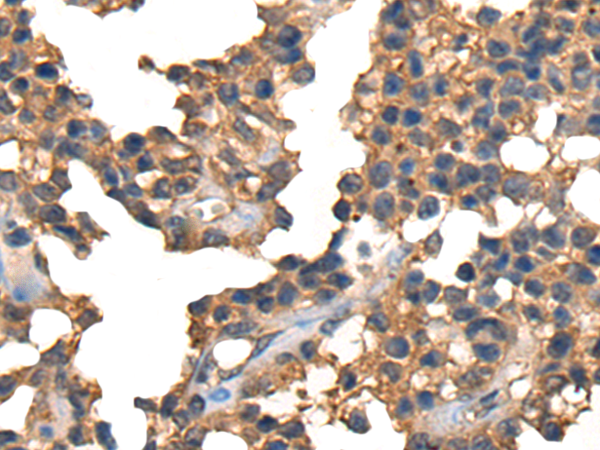

CTLA4 |

cytotoxic T-lymphocyte associated protein 4 |

IHC positive control: |

Human liver cancer and Human ovarian cancer |

IHC Recommend dilution: |

25-100 |